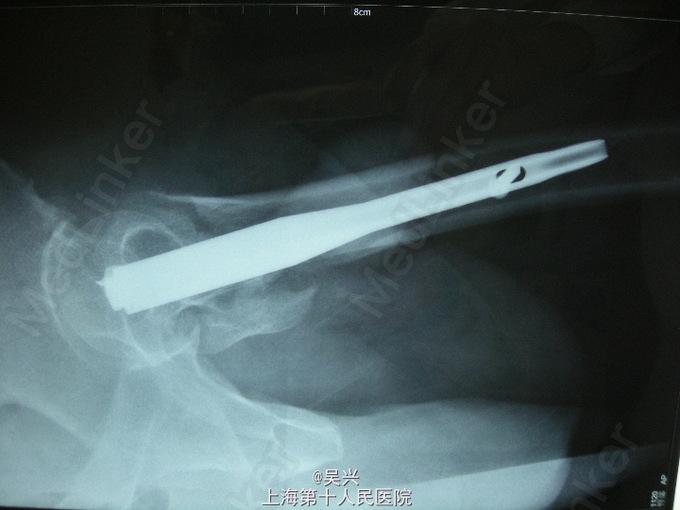

诊断:左股骨粗隆间骨折 处理:入院后予患肢皮肤牵引,完善术前准备,第3天行左股骨粗隆间骨折闭合复位、PFN-a内固定术。

随访:术后第1天,患者可坐起,翻身,术后3天可坐轮椅车外出,术后2月,骨折临床愈合可扶拐下地。 讨论:股骨粗隆间骨折是骨科常见的骨折之一,仅次于桡骨远端骨折。一般发生于高龄老年患者,如果不手术只能卧床、翻身困难,容易引起坠积性肺炎、褥疮等并发症危及生命。如果没有绝对禁忌症医生应该和患者家属充分沟通后积极手术,术前应纠正严重贫血。手术方式首选微创切口,PFN-a髓内固定,1、2型较稳定的也可选用DHS固定。术后可早期坐起翻身,防止卧床并发症。